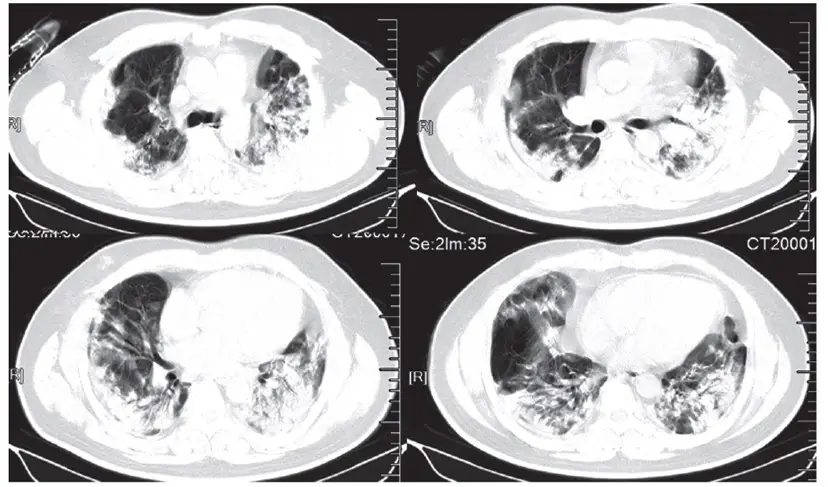

Koronavirusun Akcigerdeki Agir Tahribati Hastalarin Tomografi Goruntulerine Yansidi Video Son Dakika Flas Haberler

www.cnnturk.com

Son Dakika Corona Virusu Akcigerinin 80 Nini Kaplamisti Iyilesti Saglik Haberleri

www.sabah.com.tr

Virusun Akcigerdeki Tahribati Goruntulendi Video Son Dakika Flas Haberler

Koronavirusu Yenen Doktor Virusun Ilerleme Hizi Korku Filmi Gibi

www.aa.com.tr

Corona Dan Kurtulan Hastalarda Kalici Organ Hasari Meydana Gelebiliyor Diken

www.diken.com.tr

Iste Koronavirusun Akcigerlerde Yol Actigi Hasar Dunyadan Haberler